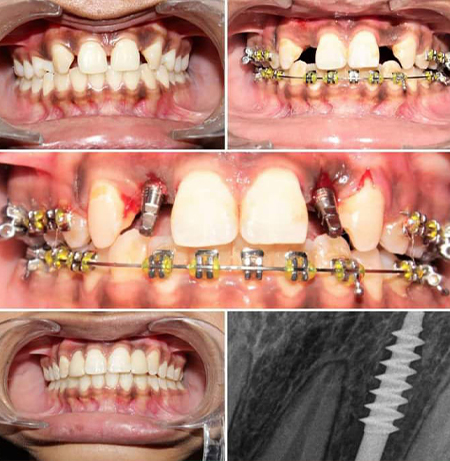

Our Photo Gallery

Before & After

Gallery Image1

Gallery Image2

Gallery Image3

Gallery Image4

Gallery Image5

Gallery Image6

Gallery Image7

Gallery Image8